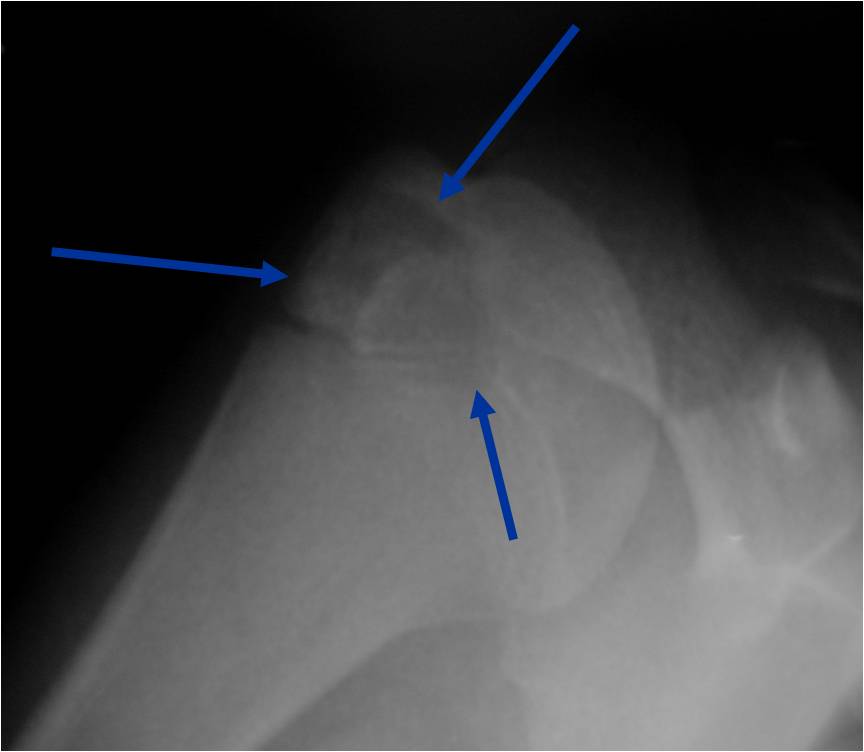

Plain x-ray appearance:

- Geographic lytic lesion IA/IB margin of sclerosis

- Usually Eccentric more often than Central in the bone

- Rarely expansile (rarely penetrates the cortex)

- Calcified chondroid matrix 30%-50% of cases

- Often better detected with a CT Scan

- Periosteal Reaction 30-50% of cases

- Usually occurs in Adjacent Diaphysis/Metaphysis since epiphysis is intraarticular and not surrounded by periosteum